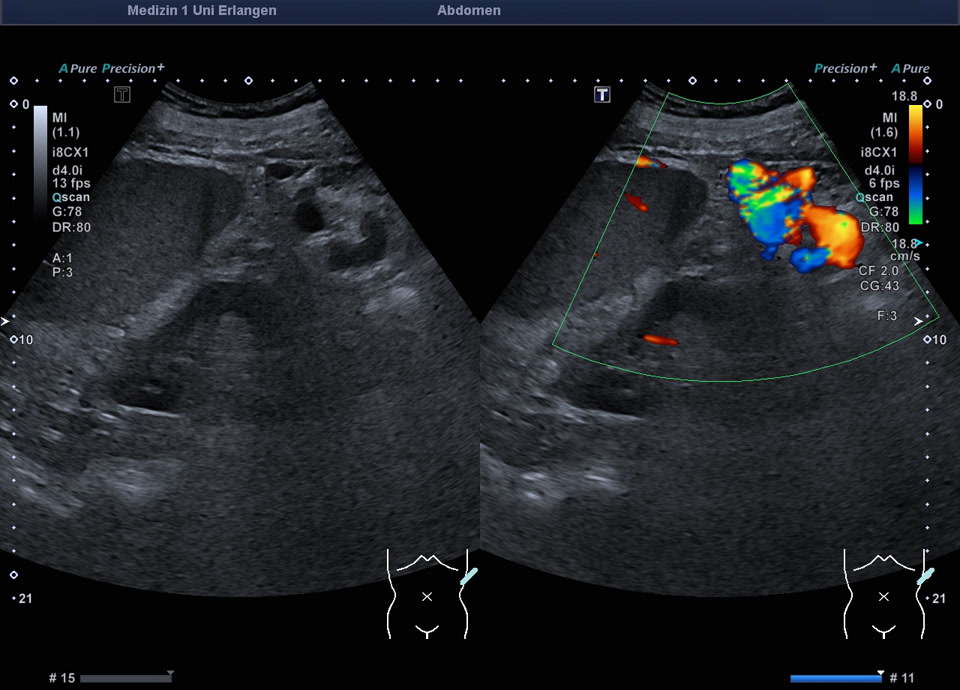

Splenomegalie